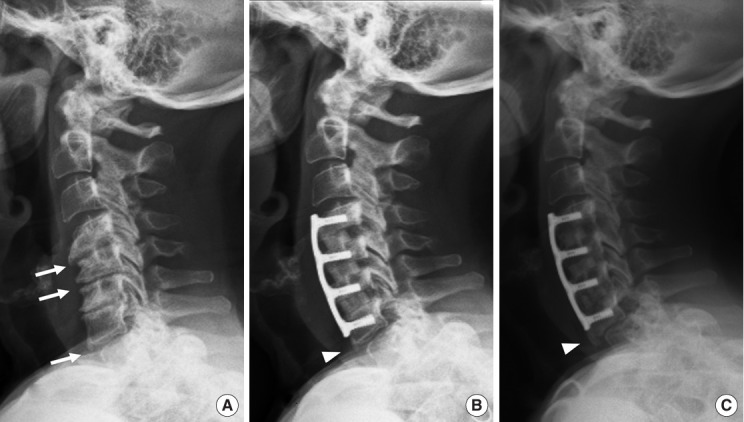

目的:探讨颈椎前路椎间盘切除术融合(ACDF)后邻接层骨化发展(ALOD)的相关因素及相关临床结果。方法:我们回顾性回顾了140例因退行性椎间盘疾病而行原发性ACDF的成年人的记录。我们比较ACDF后有和没有ALOD的患者。术前和至少24个月随访时评估影像学测量和与ALOD相关的因素。临床结果包括临床邻接节段病变(CASP)的发生率、翻修手术和患者报告的结果。结果:与颅侧和尾侧ALOD相关的因素是板到椎间盘距离短(PDD),相邻节段后凸,前凸性ACDF引起的连接节段后凸,以及术前前纵韧带骨化(OALL)。颅ALOD组的平均最终邻接节段运动范围(ROM)(6.9°±2.8°)小于无ALOD组(12°±4.2°)(p < 0.01)。尾侧ALOD组的平均最终邻接段ROM(5.5°±2.4º)也低于无尾侧ALOD组(8.2º±3.7º)(p < 0.01)。与无ALOD的患者相比,尾部ALOD患者的casp手术发生率更高(p = 0.02),而颅侧ALOD患者的casp手术发生率无差异(p = 0.69)。结论:与ALOD相关的因素是与ACDF相邻的后凸节段,前凸融合,术前OALL和短PDD。ALOD与较小的节段性ROM相关,对于尾侧而非颅侧ALOD的患者,CASP翻修手术的发生率较高。

Results: Factors associated with both cranial and caudal ALOD were short plate-to-disc distance (PDD), adjacent-segment kyphosis, hyperlordotic ACDF causing junctional segment kyphosis, and preoperative ossification of the anterior longitudinal ligament (OALL). Mean final adjacent-segment range of motion (ROM) was less in those with cranial ALOD (6.9° ± 2.8°) than in those without cranial ALOD (12° ± 4.2°) (p < 0.01). Mean final adjacent-segment ROM was also less in those with caudal ALOD (5.5° ± 2.4º) than in those without caudal ALOD (8.2º ± 3.7º) (p < 0.01). The incidence of CASP-required surgery was higher in those with caudal ALOD (p = 0.02) but no different in those with cranial ALOD (p = 0.69) compared with those without ALOD.

Conclusion: Factors associated with ALOD were a kyphotic segment adjacent to ACDF, hyperlordotic fusion, preoperative OALL, and short PDD. ALOD was associated with less segmental ROM and, for those with caudal but not cranial ALOD, higher incidence of revision surgery for CASP.